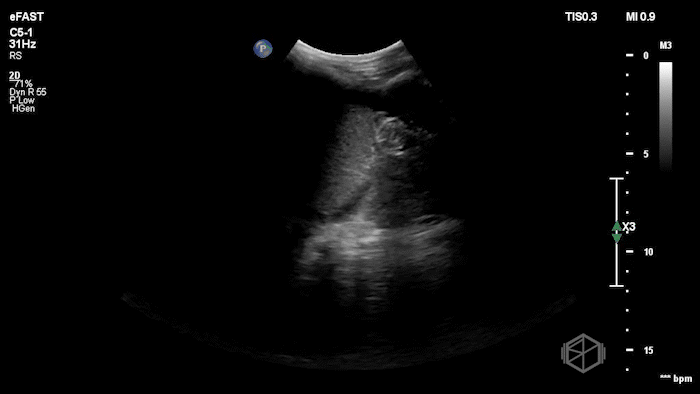

Drs. Ariz and Scavelli were caring for an approximately 40-year-old woman, G2P1, at approximately 8 weeks gestation, who presented to the ED with abdominal cramping. She was hypotensive on arrival, prompting the team to reach for the ultrasound immediately. They saw the following:

POCUS showed free fluid throughout the abdomen, including the RUQ, LUQ, and pelvis. The uterus was empty, and the final clip appears to show a complex left adnexal mass.

Diagnosis: Left ectopic pregnancy with hemoperitoneum